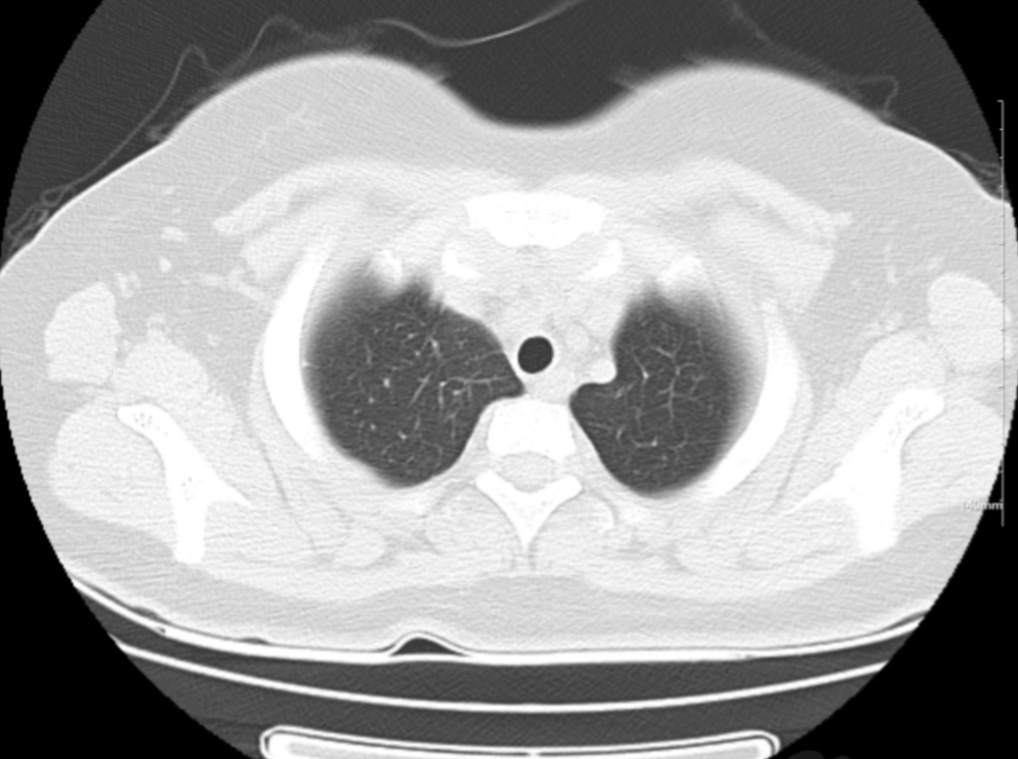

肺部CT:

支气管血管束增粗且伴 < 2 个肺叶的磨玻璃密度影, 多提示为单纯性百日咳肺炎。(下图:支气管血管束增粗, 两肺下叶基底段少许磨玻璃密度影)

如出现肺内支气管血管束增粗, 伴≥3 个肺叶斑片影、亚段性实变及支气管气象时, 提示患儿病情较重,可能合并其他感染。